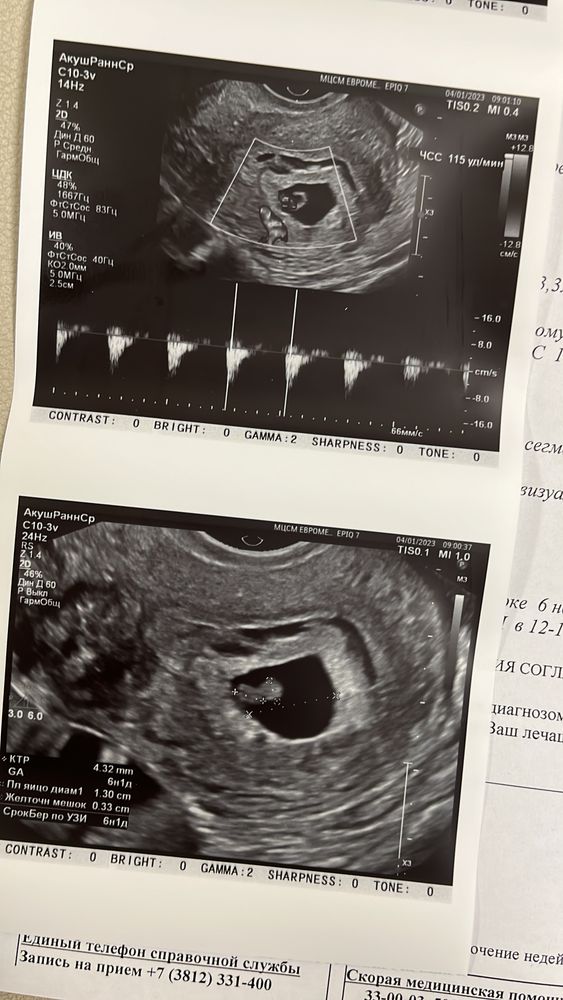

Узи на 25дпп 👼🏻❤️

Mary New, я легла на кушетку, врач смотрит на монитор и молчит. Я уже вся извелась. Она говорит «да не переживай, все хорошо, я сейчас все измерю покажу тебе». Думаю, ну ладно, жду.. А внутри то волнуюсь ппц. Потом она включила сердечко послушать на 6 секунд.. и всё, я поплыла)) Пусть у вас все будет хорошо!!!